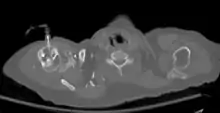

Axial CT with left humeral head EZ-IO (power driver device) infusion of contrast.

Intraosseous devices allow quick and safe access to the vascular system for fluid and drug administration. After proper education and training, medical professionals can obtain vascular access via the IO route of administration by using one of the multiple devices that have been approved by the FDA for 24-hour use.[7] There are several FDA approved IO devices, categorized by their mechanism of action:

• The EZ-IO device is a small device that works like a traditional drill and drill bit, consisting of a reusable, battery-powered driver and disposable, hollow IO needle.[15] A trigger allows for the IO needle to enter the bone marrow space at a preset length without any pressure being applied.[16] In the United States, the FDA has approved the use of the EZ-IO device in the proximal tibia and the head of the humerus.[16]